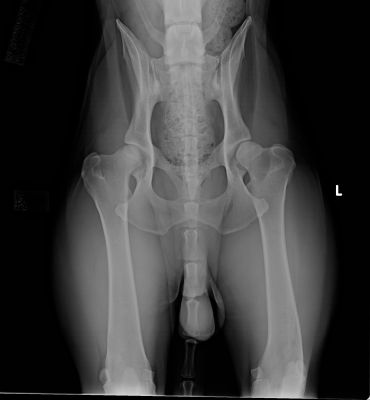

Here are some x-rays for you for evaluation. Those have been send to OFFA and I have the results at hand. So, in a way its a bit of a game

Please state your rating (good, fair, mild, moderate) and which site (right, left, both) together with why you would give this rating.

This is a male, 2 years old, fully sedated.

Right side fair to good; left side would like to see a tighter fit of femur in the socket; mild HD. Overall due to left hip; mild HD. Nan On a really good day, maybe fair.

Left knee isn't rotated like right is, obvious from the curvature on the left that isn't evident on the right, even though the knees aren't included. You can also see the knee cap is toward the center on the right side and way off on the left. I wouldn't send these in and I would expect OFA to return these and ask for a complete film. If they decided they didn't care that the xray is not correct, I'd guess unilateral mild.

A showline friend had a very similar xray go A3; one knee was rotated perfectly and one wasn't rotated much at all- it gives the appearance of one hip being significantly tighter than the other. Same dog went OFA unilteral mild due to subluxation with no arthritic changes present.

Best guess mild HD, left hip; maybe moderate because this dog is only 24 months and already showing a fair amount of changes in that hip. Remodeling (flattening of the head, widening of the joint, thickening of the neck). IMO another xray won't make any difference. Right side - fair to borderline but a moot point since OFA will always use the rating of the "worst" hip.

Yeah, you can see the patella, partly, if you really look, but I'm not sure how closely they'll look. My only point was that there is a significant difference in rotational degrees if you gauge by the visible portions of the knees, and it is known that knee caps to the outside of the film will cause the hip to look less well-seated than it should, thus downgrading a rating. Also, it shows a different angle of the hip, one that is often not as "pretty" and round as the view when the knees are rotated appropriately.

I don't see enough remodeling to say a proper xray is a moot point. If it were my dog, I would never send in an xray with the knees missing, especially if they were positioned so poorly to begin with. I'd want the full picture. People bitch and moan about straight xrays all the time but seem to gloss over KNEES which is more important as far as seating them deeply. Hans' page is the best I've seen as far as showing a variety of positions and what it does to hip presentation.